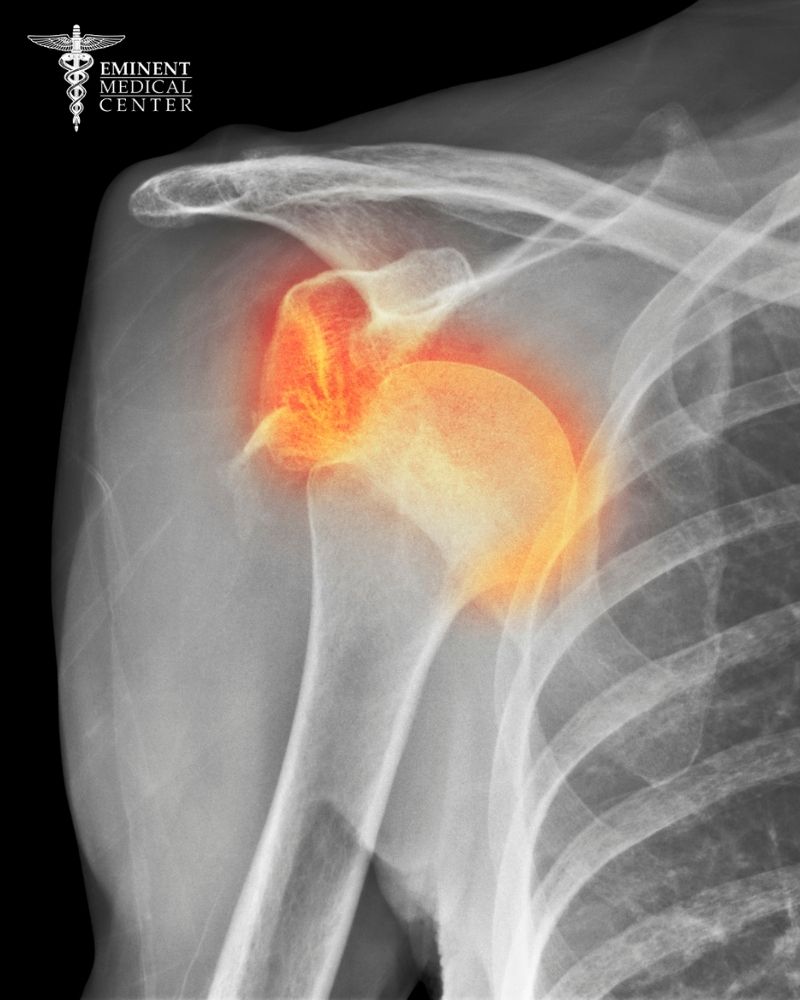

A recent NIH National Library of Medicine article states that Bankart lesions are the most common form of ligament injury in the shoulder, where the glenoid labrum (the soft cartilage around the shoulder socket) tears after a dislocated shoulder. This tear weakens the shoulder joint capsule and ligament restraint, reducing concavity compression that holds the humeral head centered like a golf ball on a golf tee. Without that support, the shoulder loses stability and becomes prone to repeated injury.

When the arm moves into certain positions and dislocates, the humeral head, the ball of the shoulder joint, can slip out of its joint space and tear the glenoid labrum from the bone. This type of tear, particularly in the lower front portion of the labrum, is known as a Bankart lesion and is the most common form of ligament injury following an anterior shoulder dislocation.

Unlike any other joint in the human body, the shoulder allows for a wide range of motion. Still, maintaining stability depends heavily on soft tissue structures like the labrum, rotator cuff, and ligaments. Once these structures are compromised, the shoulder becomes prone to recurrent dislocations. With each subsequent dislocation, the labrum and surrounding ligaments weaken further, increasing the risk of long-term shoulder instability and making recovery more difficult without surgical repair.